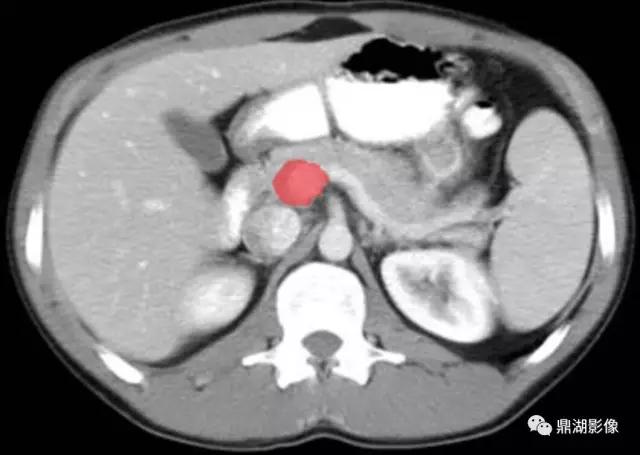

脾静脉(Splenic Vein)

肠系膜上静脉(Superior Mesenteric Vein)

肠系膜上动脉(Superior Mesenteric Artery)